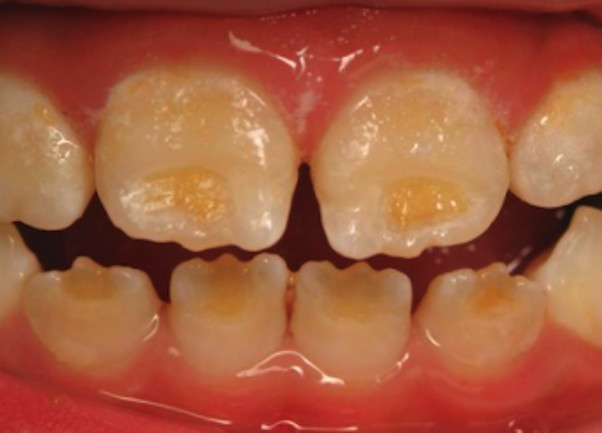

Enamel is the hard, protective outer layer of your teeth. Enamel hypoplasia is a defect of the enamel that only occurs while teeth are still developing. Still, it can affect both baby teeth and permanent teeth. The condition results in thin enamel, which makes your teeth vulnerable to dental decay.

The visual signs of enamel hypoplasia include white spots, pits, and grooves on the outer surface of the teeth.

pits, tiny groves, depressions, and fissures

white spots

yellowish-brown stains (where the underlying layer of dentin is exposed)

sensitivity to heat and cold

lack of tooth contact, irregular wearing of teeth